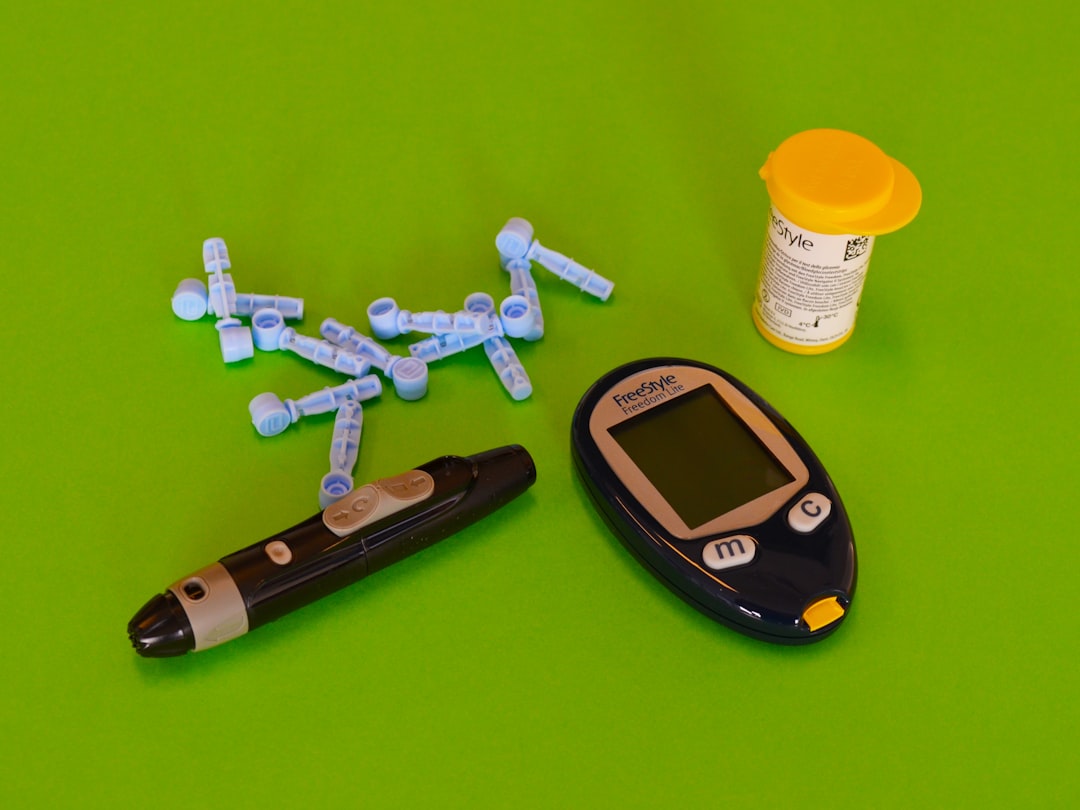

Insulin: A Pancreas Experiment Gone Right

In the late 1880s, two doctors at the University of Strasbourg, Oscar Minkowski and Josef von Mering, were researching the pancreas’ role in digestion when they removed a pancreas from a dog and noticed that afterward, flies were suddenly gathering around the dog’s urine. They tested the urine and found sugar in it. They realized that by removing the pancreas, they had given the dog diabetes.

Those two never figured out what the pancreas produced that regulated blood sugar. During a series of experiments between 1920 and 1922, researchers at the University of Toronto were able to isolate a pancreatic secretion that they called insulin. By accident, they discovered that a substance produced in the pancreas regulated blood sugar, and this breakthrough led to the treatment of diabetes, saving millions of lives worldwide.